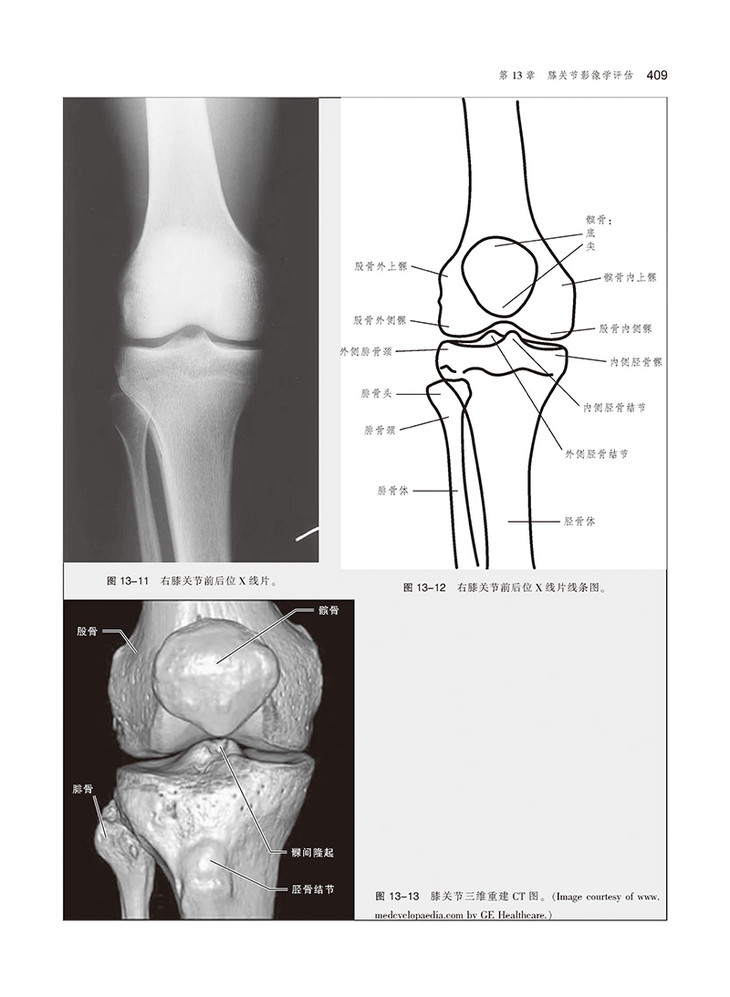

本书由美国知名物理治疗与康复专家Lynn N. Mckinnis主编。全书共18章,前3章主要阐述了影像学基础、研究方法、常见病理学基础和骨折的特征;第4~6章阐述了先进的影像学技术;第7~17章按人体各解剖部位,首先简要回顾解剖知识,接着详细介绍常规影像学技术和先进影像学技术,最后通过这些影像学技术,介绍了人体各部位最常见的外伤和病理学内容;最后一章为“影像学与物理治疗实践的结合”,探讨了影像学在物理治疗实践中的应用。本书结构清晰,内容翔实,适用于影像科医师、物理治疗医师及康复医师等参考阅读。

本书每章均包含骨骼学和结缔组织基本结构概述,并加入了CT和MRI等影像学新技术,对读者需要了解的特殊病理学知识也进行了阐述。这种编排方式使得读者不论从哪个章节入手,均易于理解本书的内容。本书各章末均包含人体各部位最常见的外伤和病理学内容,并给出具体病例解析,包括病史、影像检查和体格检查、治疗和预后等,且均有图示。各章末还有 “要点总结”和 “自测”内容,有助于读者抓住重点,并通过图像解读,考察自身实践能力。

•MRI解剖部分可使读者了解关节各层面的断层解剖结构,且对重点解剖结构做了标注。

•各章末设置了“自测”练习,可使读者通过X线片,了解关节的正常解剖结构及不同病理学改变。